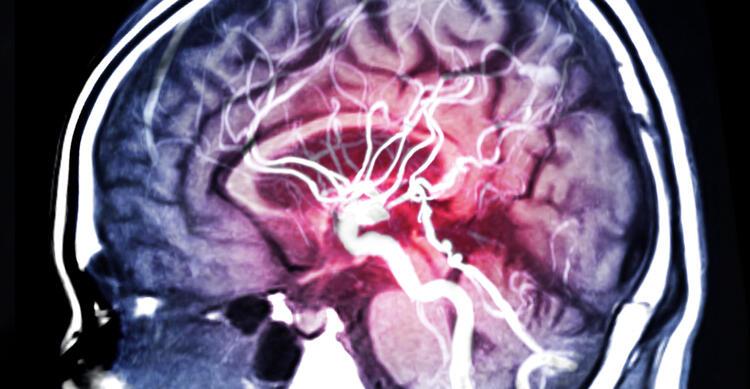

- Ancak teşhis ve tedavilere karşın genç adamın durumu kötüleşmeye devam etti ve sık sık nöbet geçirme ve göz kararması çekmeye başladı. Tümörün niteliği ve neden geliştiğini araştırmaya başlayan doktorlar şoke edici bir gerçekle karşılaştılar. Whag Lei’nin beyninde 12 santimetre uzunluğunda bir tenya yaşıyordu. 2018 yılında, doktorlar Lei’nin beyninde tenya yaşadığını keşfetti ve hastaya parazitin işlem yapmasının riskli bir bölgede olduğu düşünüldüğü için cerrahi olmayan bir tedaviye başlaması önerildi. Ancak ilaçlı tedavi işe yaramayınca ameliyat kaçınılmaz oldu.

- Guangdong Sanjiu Beyin Hastanesi’nde 2 saatlik ameliyatın ardından, sağlık görevlileri raporlara göre, kedilerin ve köpeklerin bağırsaklarında yaygın olarak bulunan fakat nadiren insanlarda görünen Sparganum mansoni paraziti çıkardılar. Ameliyatı yapan doktorlar, “Canlı tenya beyinde hareket ediyordu ve hepsini çıkarmak zorunda kaldık, aksi halde kalan kısım tekrar büyüyebilirdi” açıklaması yaptı. Parazitlerden nasıl korunmak gerekir? İnsanlar, iyice pişirilmesi gereken kurbağaları, salyangozları ve yılanları pişirirken dikkatli olmalıdırlar. Ayrıca, kaynatılmadıkça doğal ortamlardan su içmeyin.(Posta)